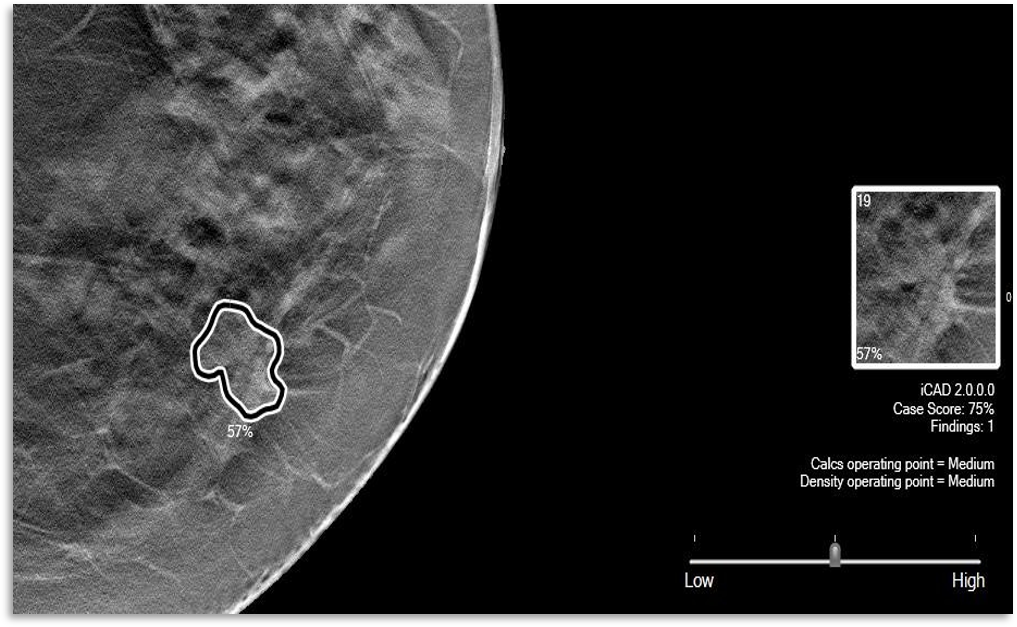

ProFoundAI®contoure les lésions suspectes directement sur les images de mammographie 2D et 3D affichées sur la station de lecture ou du PACS. Pour chaque lésion, un score allant de 1 à 100 % indique la certitude qu’à l’algorithme sur la malignité de la lésion suspecte. De plus, un score général est également produit.

ProFound AI Détection pour la mammographie 2D

mammographie 2D